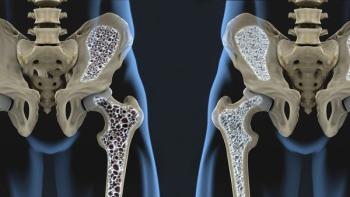

The use of tramadol in older patients is associated with a higher risk of hip fracture compared with the use of codeine or commonly used nonsteroidal anti-inflammatory drugs (NSAIDs), say researchers recently writing in in the Journal of Bone and Mineral Research.